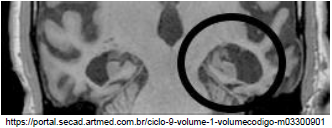

Observe a imagem abaixo.

A atrofia da região assinalada na imagem acima, é encontrada em qual tipo de demência?